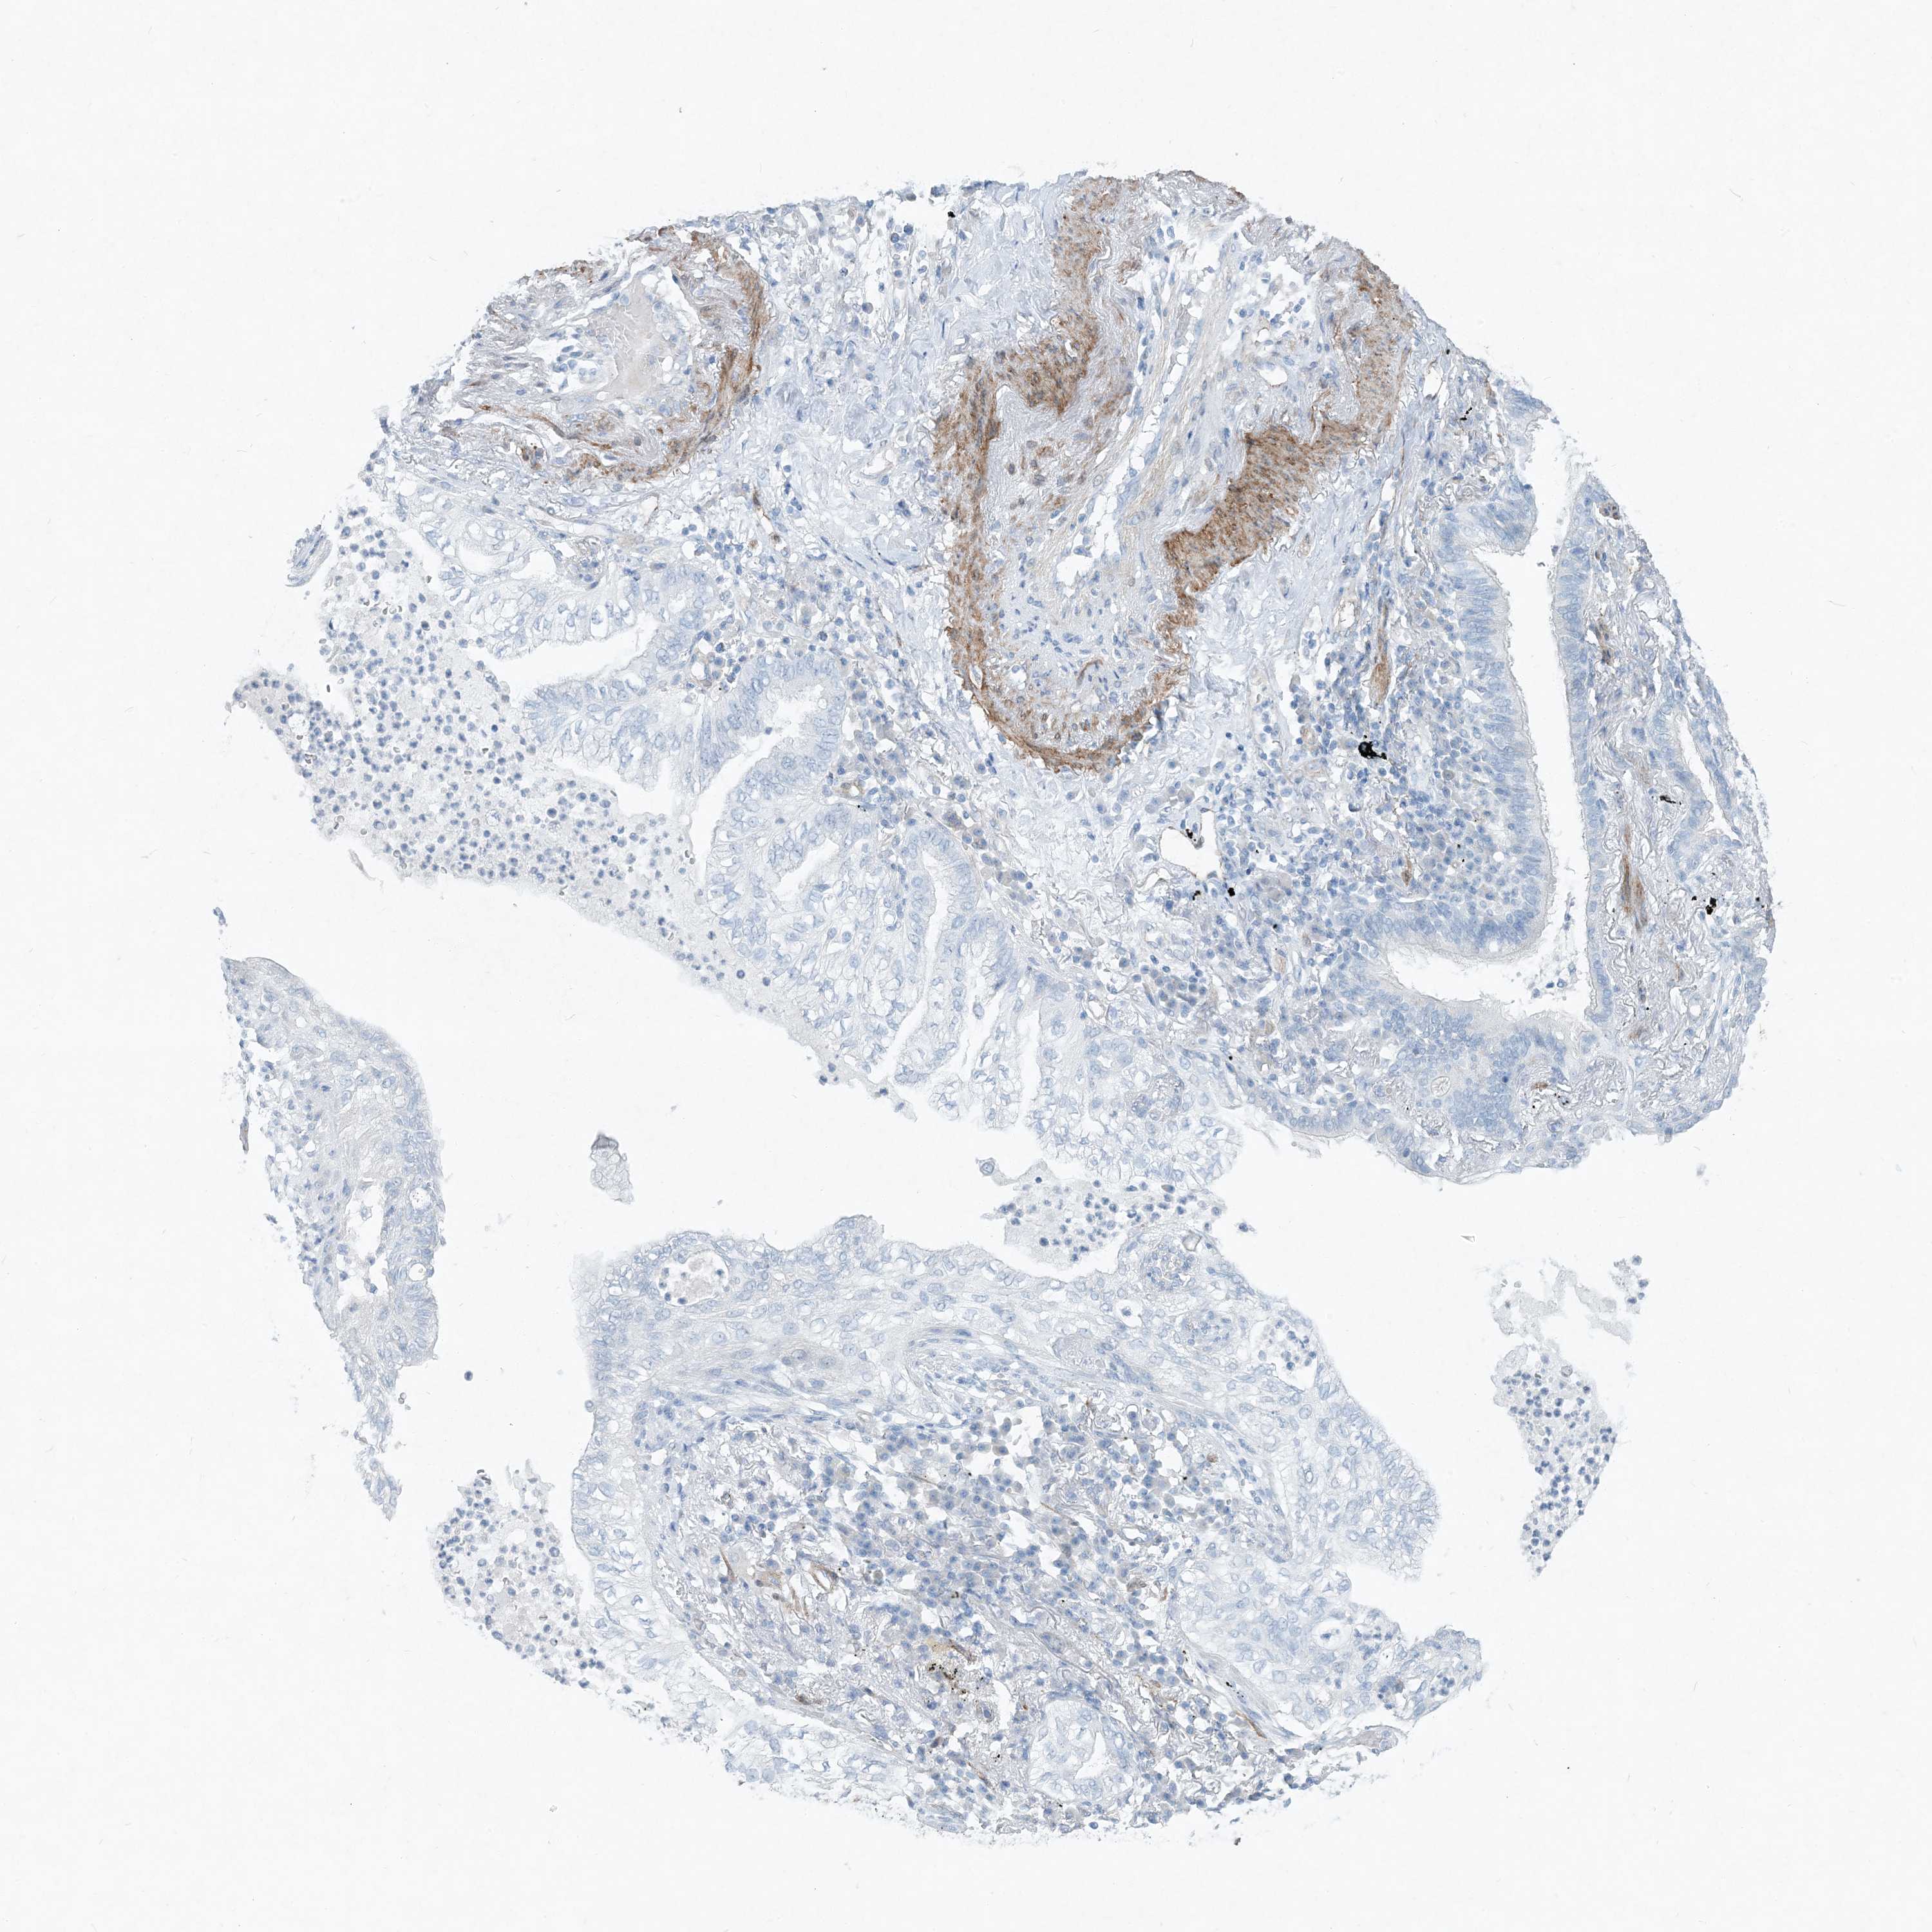

CANCER LUNG CANCER Show tissue menu

LUAD TCGA LUAD VALIDATION LUSC TCGA LUSC VALIDATION PROTEIN LUAD CPTAC PROTEIN LUSC CPTAC PROTEIN EXPRESSION